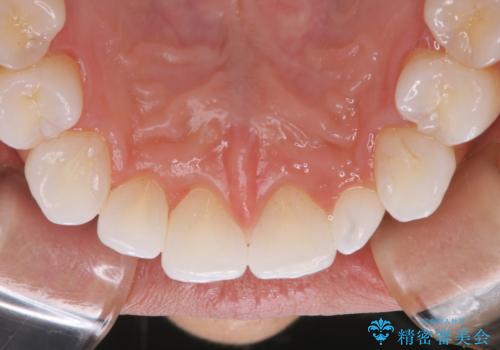

PMTC30分コースを行いました。

PMTCは審美的な面だけではなく、虫歯や歯周病予防にもなります。虫歯や歯周病予防のためには、お口の中を清潔に保つことが大切です。